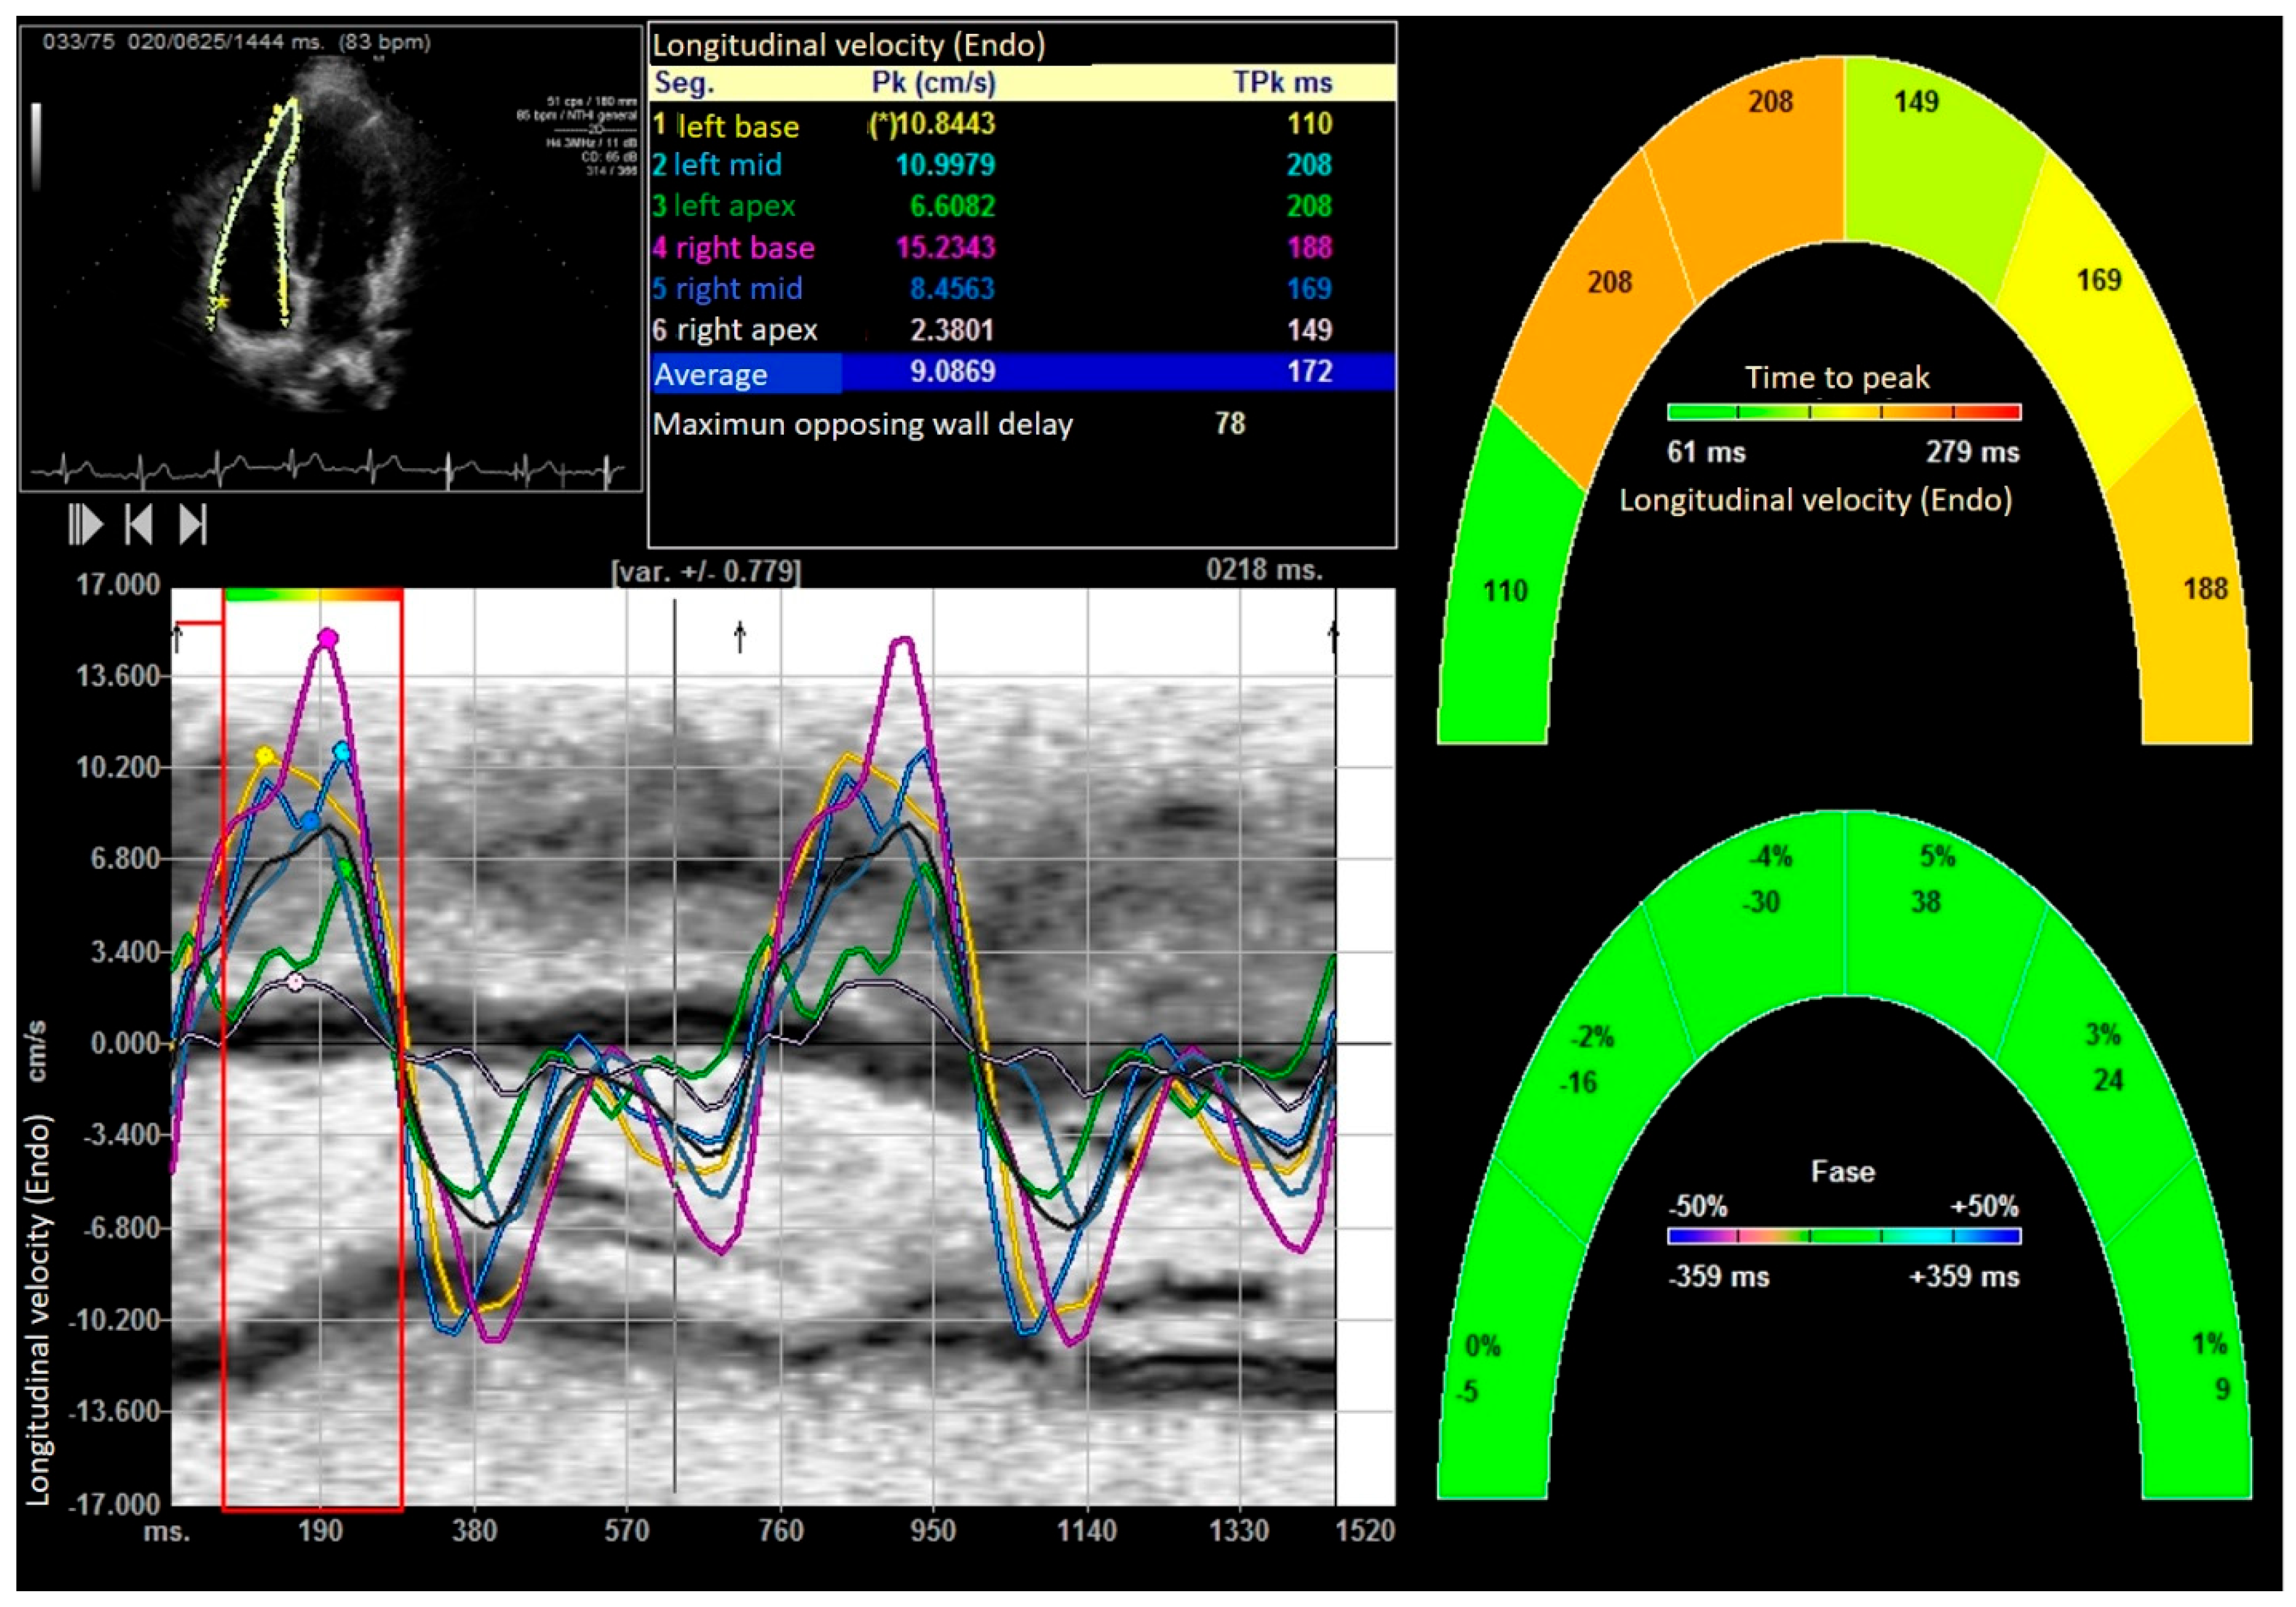

| Peak systolic longitudinal velocity (cm/s) | 4.98 ± 0.12 | 4.01 ± 10.21 | 9.48 ± 3.25 | 0.001 |

| peak E longitudinal velocity (cm/s) | −5.6 ± 1.35 | −4.2 ± 0.87 | −7.38 ± 3.15 | 0.0001 |

| peak A longitudinal velocity (cm/s) | −4.01 ± 0.74 | −3.75 ± 0.98 | −5.14 ± 1.48 | 0.0001 |

| Peak systolic radial velocities (cm/s) | 4.76 ± 0.48 | 1.76 ± 0.48 | 6.17 ± 1.35 | 0.0001 |

| E peak radial velocity (cm/s) | −1.75 ± 0.16 | −1.45 ± 0.54 | −2.21 ± 0.191 | 0.0001 |

| A peak radial velocity (cm/s) | −0.11 ± 0.12 | −0.09 ± 1.35 | −0.6 ± 0.22 | 0.0001 |

| Right ventricular longitudinal global strain (%) | −27.31 ± 1.47 | −23.55 ± 2.37 | −30.98 ± 2.12 | 0.0001 |

| Right ventricular Longitudinal Strain delay (ms) | 144.88 ± 22.52 | 168.92± 29.35 | 98.27 ± 12.11 | 0.0001 |

| Right ventricular longitudinal global right Strain rate (1/s) | −1.79 ± 0.078 | −1.48 ± 0.33 | −2.88 ± 0.25 | 0.0001 |

| Right ventricular Longitudinal systolic displacement (mm) | 6.12 ± 1.18 | 5.09 ± 3.22 | 10.88 ± 1.25 | 0.0001 |

| Right ventricular Radial systolic displacement (mm) | 1.88 ± 1.78 | 1.33 ± 1.14 | 4.57 ± 0.96 | 0.0001 |

| Right ventricular Radial displacement delay (ms) | 182.14 ± 17.12 | 212.36 ± 18.96 | 124.32 ± 15.25 | 0.0001 |